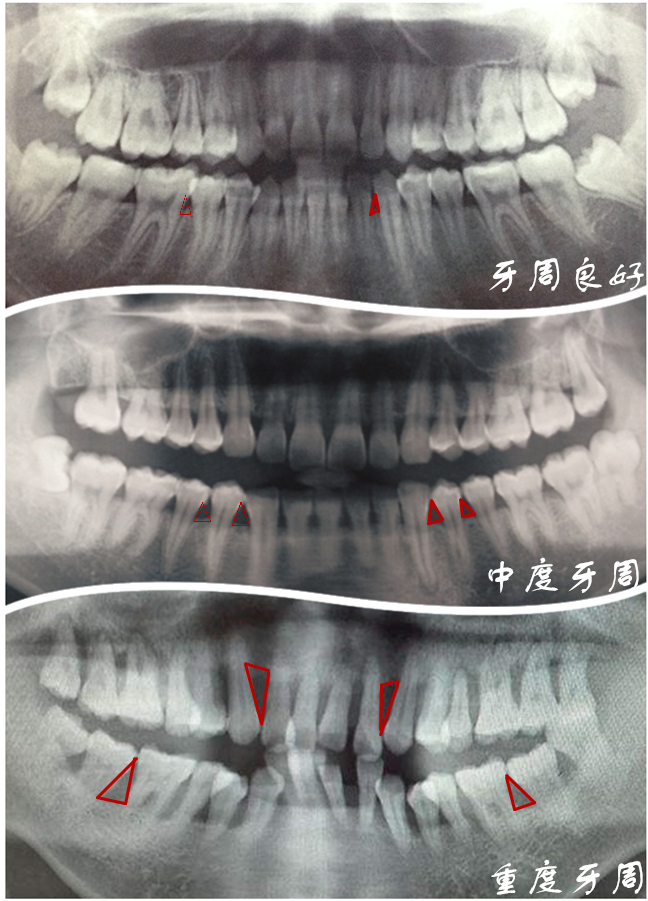

648x901 - 495KB - JPEG

牙槽骨萎缩